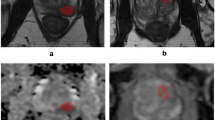

Prostate cancer represents the most common cancer afflicting men. It may be asymptomatic at the early stage. In this paper, we propose a methodology aimed to detect the prostate cancer grade by computing non-invasive shape-based radiomic features directly from magnetic resonance images.

We use a freely available dataset composed by coronal magnetic resonance images belonging to 112 patients. We represent magnetic resonance slices in terms of formal model, and we exploit model checking to check whether a set of properties (formulated with the support of pathologists and radiologists) is verified on the formal model. Each property is related to a different cancer grade with the aim to cover all the cancer grade groups.

The experimental analysis demonstrates the effectiveness of radiomics and formal verification for Gleason grade group detection from magnetic resonance.